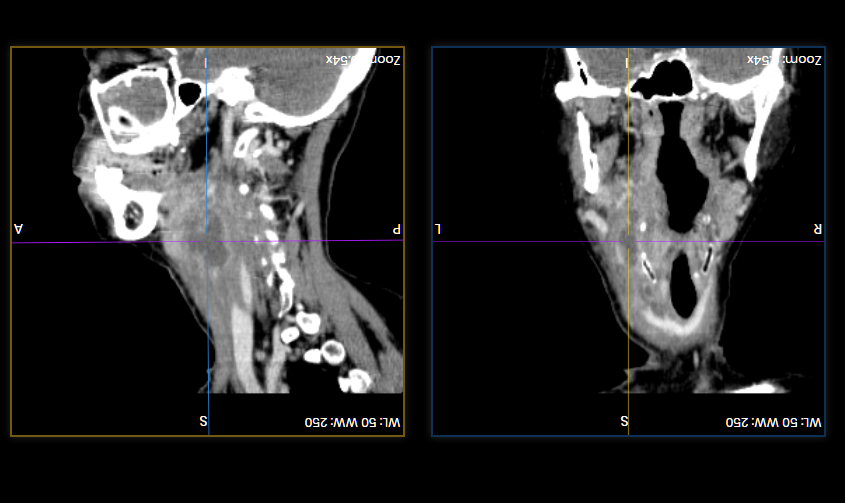

Chúng tôi mô tả một trường hợp bệnh cấp cứu đồng thời áp-xe tuyến giáp kèm nhiễm trùng cổ sâu ở khoang trước sống và khoang nguy hiểm. Bệnh nhân nữ Đ.T.N. Hương, 56t, có bệnh lý đái tháo đường không điều trị thường xuyên. Bệnh nhân không có tiền sử hóc xương, không có tiền sử bệnh lý tuyến giáp trước đó. Bệnh nhân có biểu hiện nuốt đau, kèm sưng nề vùng cổ, sờ thấy khối cứng, sẫm màu, không di động. Siêu âm vùng cổ cho kết quả vùng sau trên thùy giáp trái, trước thực quản có ổ tụ dịch nhiều hồi âm, giới hạn ít rõ, kích thước 23x30x51mm. Hình ảnh chụp cắt lớp vi tính cho thấy ổ áp-xe mô mềm lan rộng thành sau họng, kích thước 27 x 13mm, thâm nhiễm xung quanh. Bệnh nhân được tiến hành mổ cấp cứu dẫn lưu hai ổ áp-xe tránh gây biến chứng chèn ép đường thở và tránh gây nhiễm trùng lan tỏa vào trung thất, nguy hiểm đến tính mạng. Chẩn đoán vi khuẩn gây bệnh dựa vào kết quả lấy dịch mủ nuôi cấy, cho thấy nhiễm khuẩn Klebsiella pneumoniae có ESBL dương tính (men beta lactamase phổ rộng). Điều này có nghĩa vi khuẩn kháng lại rất nhiều các kháng sinh. Đây là gánh nặng thực sự trong điều trị nhiễm trùng trực khuẩn Gram âm, gia tăng chi phí điều trị do phải bắt buộc thay thế các kháng sinh cũ bằng các kháng sinh mới đắt tiền. Hiện tại, tình trạng nhiễm trùng và áp-xe được điều trị ổn định sau khi mở cạnh cổ dẫn lưu và điều trị phối hợp kháng sinh tích cực kèm súc rửa chăm sóc hố mổ hằng ngày.